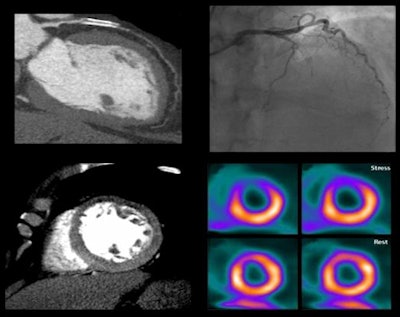

The accuracy of 320-detector-row coronary CT angiography (CTA) combined with CT perfusion (CTP) is equivalent to that of SPECT myocardial perfusion for diagnosing functionally significant coronary artery disease, according to results of the prospective, multicenter, international CORE320 trial published in the European Heart Journal.

The accuracy of CTA for detecting flow-limiting disease was substantially improved with the addition of CT perfusion, wrote Dr. Carlos Rochitte, from the University of São Paulo Medical School in Brazil, and colleagues at 15 other centers in eight countries.

Both invasive coronary angiography and CTA provide morphologic data, but they lack the physiologic information needed to determine the hemodynamic significance of a lesion. Proving that functional significance requires either catheter-based fractional flow reserve techniques, or noninvasive modalities such as SPECT myocardial perfusion imaging (MPI), PET, or MRI, the authors explained (Eur Heart J, November 19, 2013).

For detecting or excluding flow-limiting coronary artery disease, combined CTA-CTP showed an area under the curve (AUC) of 0.87 for all patients. In patients without prior myocardial infarction, AUC was even higher at 0.90, and in patients without any prior coronary artery disease, AUC was 0.93. For a patient with 50% or greater stenosis and a perfusion deficit at CTP, the sensitivity and specificity of CTA-CTP were 80% and 74%, respectively.

Meanwhile, the prevalence of obstructive CAD defined by angiography and SPECT was 38%; by angiography alone, prevalence was 59%. The median radiation dose was 11 mSv for the combined CTA-CTP tests, according to Rybicki, who said that detailed radiation exposure results will be available in an upcoming publication.

Combined CTA-CTP underestimated coronary artery disease in 29 patients (false-negative results) and overestimated CAD in 61 patients (false-positive results), compared with the combined outcome of angiography and SPECT, the group reported.